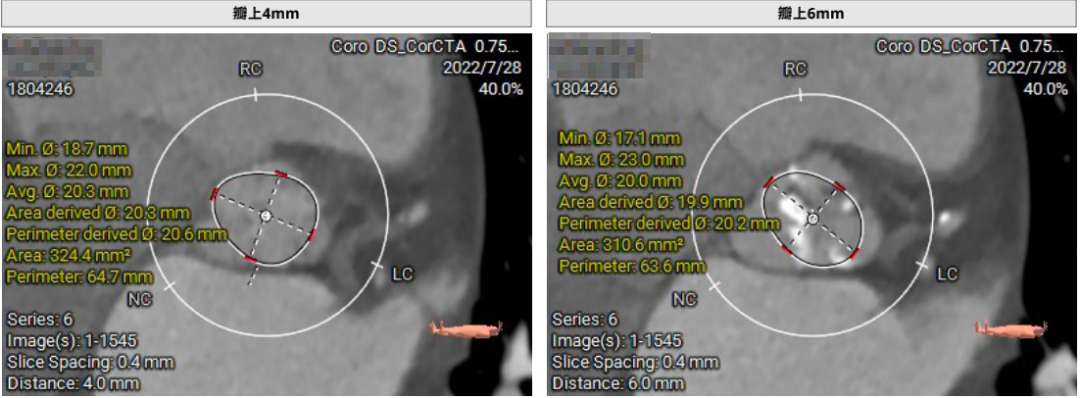

患者71岁女性,诊断为主动脉瓣重度狭窄合并心功能不全,瓣口面积仅0.5cm²,跨瓣压差超过50mmHg,且EF仅27%,心功能极差。术前CT检查瓣环周长72.2mm,LVOT呈喇叭型。CT检查同时发现患者入路血管狭窄,股动脉直径5.3cm,锁骨下和颈内动脉直径都小于5.0cm,对操作造成了一定困难。

患者64岁男性,Type 0 型二叶瓣、横位心。主动脉瓣中度狭窄,重度反流,瓣环周长92.0mm,平均径29.0mm。LVOT周长98.7mm,升主扩张,窦部结构极限,锚定能力极限。入路两侧血管轻度迂曲,分叉高度可,两侧血管内径均>8mm。

首先,最重要的是观察瓣环结构,理论上如果瓣环周长超过85mm,尽量就不做;第二,看流出道情况,最好是直筒状的,瓣环和瓣下4mm的直径比值,理论上不能超过1:1.1,如果超过1.1以上就变成喇叭状,也不建议做;第三,避免存在升主动脉显著扩张,如果扩张明显,无法提供有效的锚定。总体来说,最主要的一定是瓣环直径,瓣叶有没有增厚,瓣叶有没有钙化,瓣环能否有效固定住植入的瓣膜。瓣环的固定和锚定条件,是反流患者能否进行TAVR的决定因素。